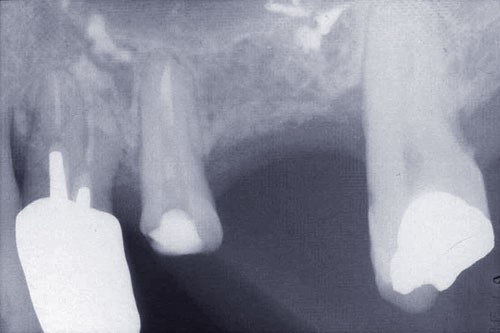

Une patiente âgée de 45 ans consulte à la fin des années 1990 avec une contention en échelle au maxillaire afin de soulager les mobilités des dents antérieures.

Les examens cliniques et radiographiques montrent une parodontite chronique généralisée (fig. 1a à m).

Nous décidons d’entreprendre une thérapeutique initiale parodontale classique dans tous les secteurs, y compris l’extraction de 24, un bridge de 45 à 48 avec 46 en pontique, un bridge complet de contention de 17 à 27 sur 11 piliers dentaires et une greffe épithélio-conjonctive sur 31. Cette dernière ne sera jamais réalisée. Le bridge maxillaire permettra de réduire le surplomb antérieur et d’améliorer le sourire de la patiente, ce qui constitue l’une de ses demandes.